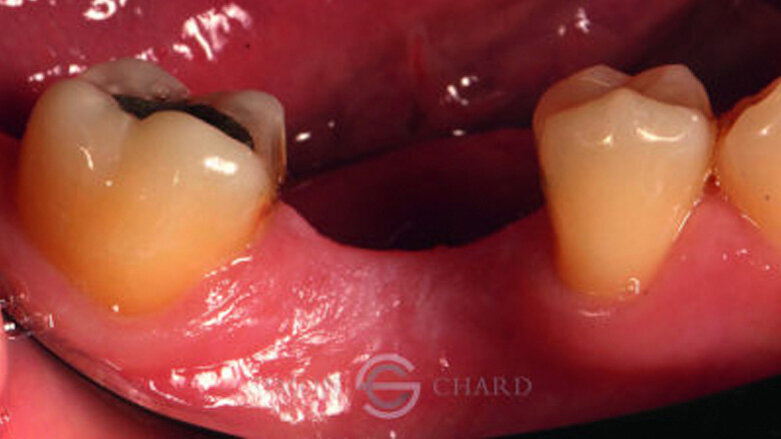

This case report highlights a novel method of restoring implants utilising the modern advances in digital intraoral scanning and chairside milling. It illustrates how an aesthetic single implant retained crown can be provided chairside without the need for analogue impressions (Figs. 1 & 2: Pre-operative condition).

Following a discussion of the options for replacement of LR6, the patient elected for an implant-retained solution. A MegaGen AnyRidge 4 x 10 mm implant was placed utilising a surgical guide for position of the pilot hole. An immediate temporary crown was fabricated using the MegaGen fuse abutment and DMG Luxatemp. A silicone index of the diagnostic wax-up was fabricated and the temporary crown was polished and taken out of occlusion while the implant fully integrated (Fig. 3).